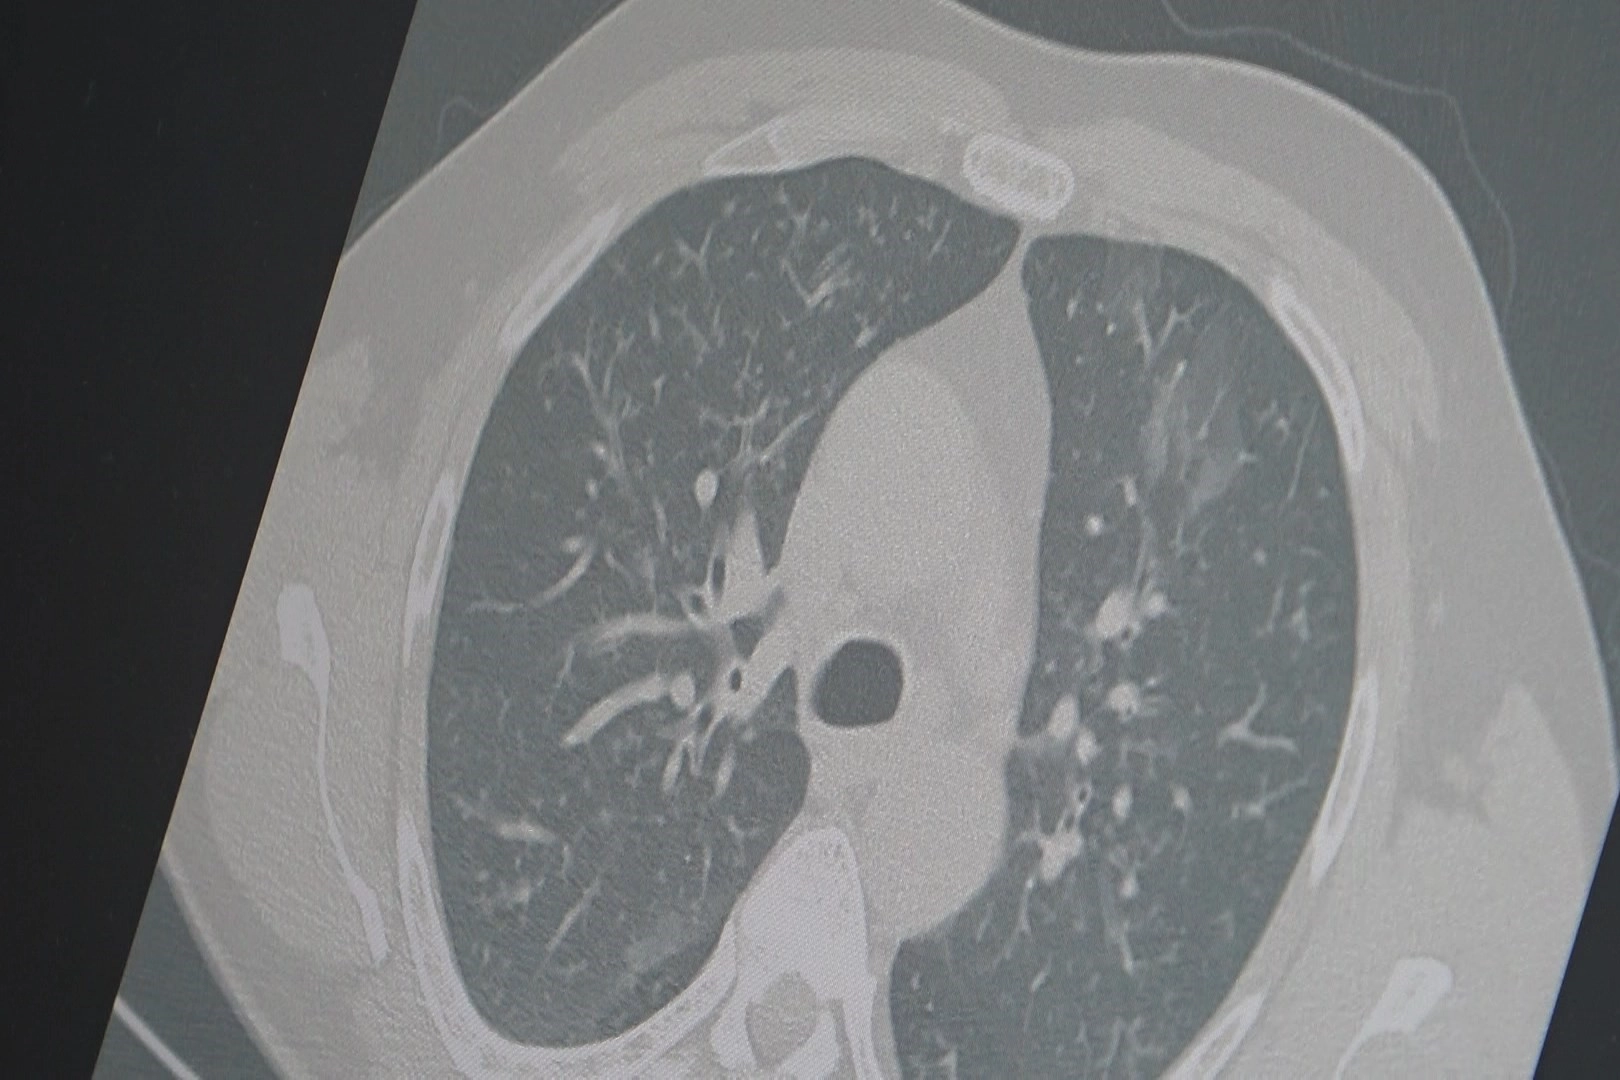

Zatürre riski arttıGrip ve kovid-19’un bazı hastalarda akciğerlere inerek zatürreye yol açabildiğini vurgulayan Özkaya, “Son haftalarda hastaneye yatışlarda artış görüyoruz. Uzayan öksürük ve nefes darlığı yaşayanlar mutlaka doktor kontrolüne başvurmalı” dedi.